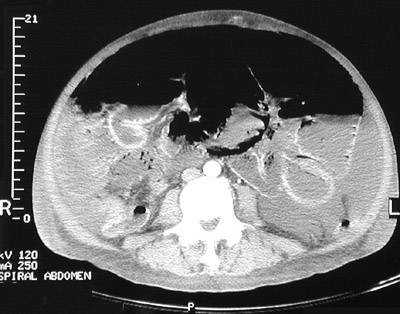

| The abdominal CT scan views above and below demonstrate the uncommon condition known as pneumatosis intestinalis in which small collections of air (seen here as black spaces) appear in the bowel wall. These scan also reveal a large amount of ascitic fluid as well as free air in the abdomen. |